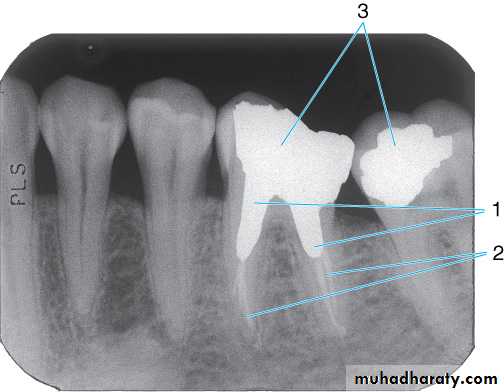

Dental materials. This radiograph shows several metallic and non-metallic dental materials. Since all of the metal restorations are equally radiopaque, their size and shape is observed to determine the type of material. The materials present in this radiograph are: (1) amalgam;(2) porcelain-fused-to-metal crown; (3) post and core; (4) gutta percha; (5) base material; (6) full metal crown, which is the posterior abutment of a three-unit bridge; (7) retention pin; and (8) metal pontic (part of the three-unit bridge).